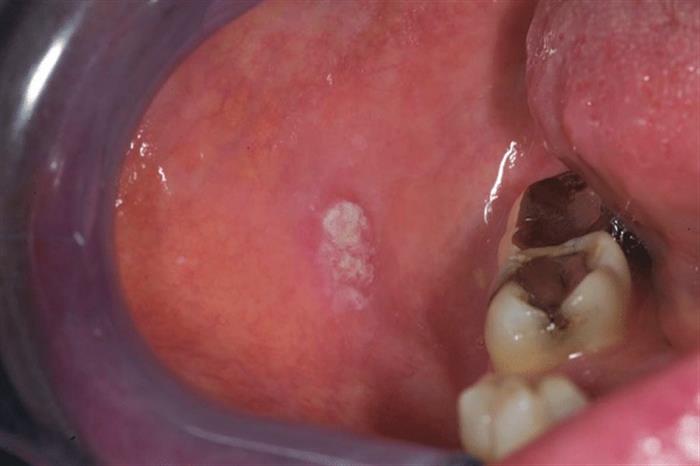

سرطان تجويف الفم

يعتبر سرطان الغشاء المخاطي لتجويف الفم من الأمراض التي يصعب اكتشافها مبكرًا، لأن أعراضه عادةً لا تظهر في المراحل الأولية، حسبما ذكرت طبيبة الأسنان، إيريكا سوتنيكوفا.

وأضافت إيريكا أن سرطان الغشاء المخاطي لتجويف الفم يظهر على شكل عقد أو تقرحات، تتضخم وتصبح مثيرة للألم مع تطور المرض.

وأوضحت أن أعراض سرطان تجويف الفم الرئيسية تشمل:

- جفاف الفم.

- رائحة الفم الكريهة.

- تضخم الغدد الليمفاوية في الرقبة.